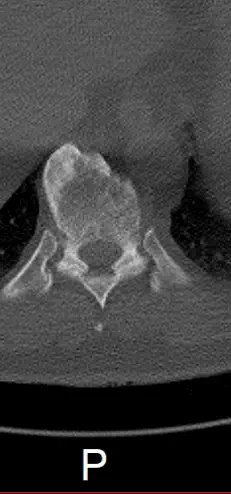

Osteoplastische Knochenmetastasen zeichnen sich dadurch aus, dass Krebszellen den Knochen angreifen und eine übermäßige Bildung von neuem Knochengewebe anregen, was zu einer Verdichtung und Sklerosierung des Knochens führt. Die jedoch die Knochenstabilität nicht verbessert. Die im Gegensatz zu Osteolytische Metastasen bei denen Knochen abgebaut wird. (Zum Beispiel Löcher, dünne Knochen und dünne Knochenränder)